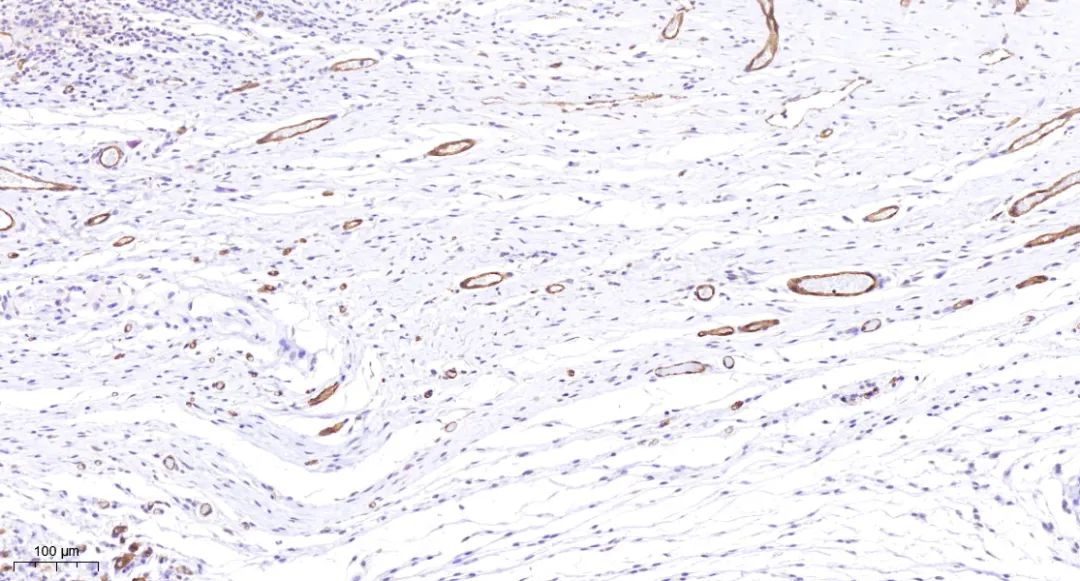

免疫组化是基于免疫学基本原理——抗原抗体反应,即抗原与抗体特异性结合的原理,通过化学反应使标记抗体的显色剂显色来确定组织细胞内抗原,对其进行定位、定性及定量研究。

免疫组化具有特异性强、敏感性高、定位准确、形态与功能相结合等多种优点。

免疫组化可应用于确定细胞类型、发现微小转移灶、了解分化程度 、临床应用、肿瘤起源与分化 、指导治疗与预后等多个方面。

免疫组化实例·皮

免疫组化实例·瘤